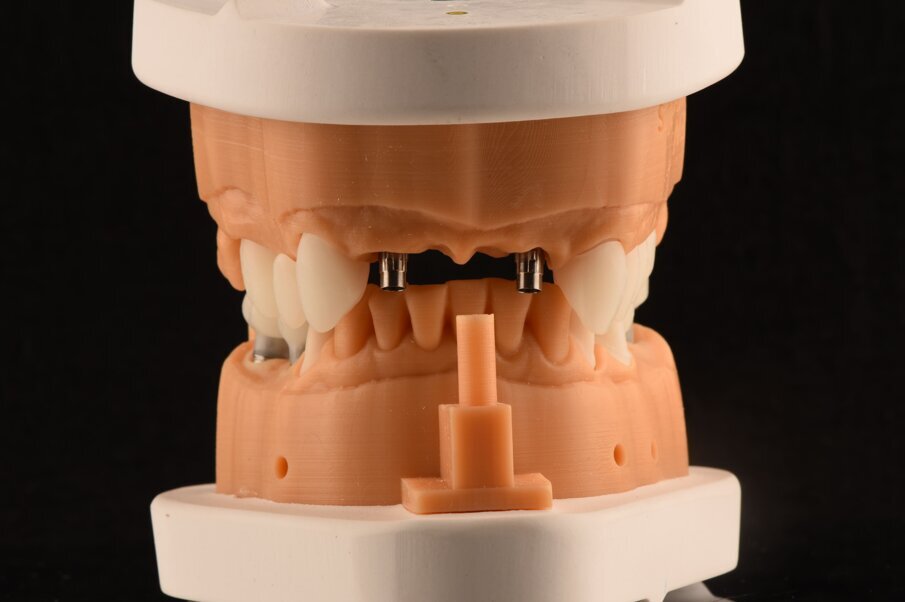

La rigenerazione ossea è stata ottenuta secondo l’impiego di biomateriale di origine bovina demineralizzato e stabilizzato con una membrana a lento riassorbimento in pericardio nativo fissata con dei chiodini in titanio (Fig. 23). Com’è noto la stabilità dell’innesto è un requisito indispensabile per ottenere una reale rigenerazione ossea stabile nel tempo. Dopo 4-6 mesi si effettua una radiografia di controllo eseguendo successivamente un opercolo perimplantare. In questo caso data la lieve deiscenza presente si è optato per l’impiego di un diatermocoagulatore per limitare il danno biologico ai tessuti limitrofi e mantenere inalterata la rivascolarizzazione della sede, inoltre non essendo un materiale metallico ma bensì ceramico, l’eventuale contatto viene disperso e non assorbito dall’impianto (Fig. 24). Data l’ottima stabilizzazione funzionale e volendo contenere i costi viene realizzata un’impronta digitale dell’arcata col primo provvisorio in situ e alla sua rimozione un’impronta dell’intera arcata con e senza gli scan body implantari (Fig. 25). Per mantenere l’opercolo ottenuto si utilizzano delle cappette di guarigione sempre in Zirconia che serviranno anche per stabilizzare i tessuti perimplantari (Fig. 26). In laboratorio, l’odontotecnico su nostra indicazione potrà elaborare i file ricevuti, valutando la possibilità di avvitare direttamente il manufatto, solo in caso di forte disparallelismo si opterà per la cementazione. Definita la procedura, verrà realizzato solo il provvisorio su impianti modificando il primo provvisorio che sarà riposizionato dopo il sezionamento dei quadranti (Figg. 27, 28). Dopo il posizionamento del nuovo provvisorio rileviamo una nuova impronta studio (Fig. 29) che analizziamo col software dedicato dello scanner digitale utilizzato.

I dati raccolti sono molti ma la procedura digitale consente di sommarli e confrontarli senza limiti e indicando le possibili migliori e correzioni lungo il percorso. Dopo un breve periodo di condizionamento dei tessuti (Fig. 30) rileviamo l’impronta master per la finalizzazione ultima della riabilitazione protesica. L’impronta degli elementi naturali viene rilevata posizionando dei fili detrattori secondo la tecnica del doppio filo mentre per gli impianti verranno usati gli scan body dedicati (Fig. 31). Le potenzialità digitali consentiranno di avere una stabile lettura della posizione di centrica rilevandola prima della rimozione dei provvisori e sovrapponendola a provvisori rimossi (Fig. 32). In laboratorio l’odontotecnico realizza i modelli (Figg. 33, 34) sovrappone le immagini (Fig. 35) e raccoglie gli elaborati dei vari passaggi che porteranno alla finalizzazione del progetto digitale (Figg. 36, 37). Gli impianti in Zirconia non offrono molte soluzioni protesiche, è importante che il loro posizionamento tenga conto di quest’aspetto mettendo l’odontotecnico nelle condizioni più favorevoli (Fig. 38). Questa sistematica prevede l’uso di un moncone in titanio cementato nella struttura protesica che permette l’avvitamento all’interno dell’impianto. Nella connessione implantare è presente un’intercapedine dove alloggia il collarino in titanio del T-base totalmente inglobato all’interno della zirconia, evitando comunicazioni coi tessuti adiacenti. Va comunque considerato l’aspetto tecnico importante legato allo spessore della struttura in zirconia che deve avvolgere l’intero moncone in titanio. (Fig. 39, 40).

Fig. 33_Modelli realizzati in resina e montati in articolatole a valori medi.

Fig. 34_Dettaglio del modello superiore con la visione palatale, con i monconi t-base da ancoraggio per elementi CAD/CAM.